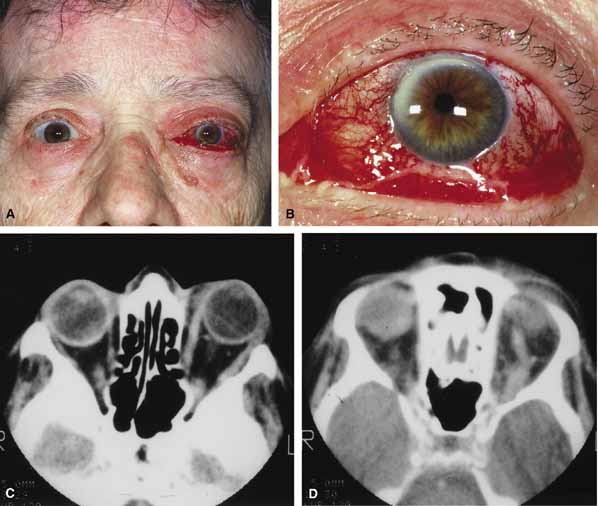

Although there have been a few reports of mucormycosis occurring in healthy individuals, virtually all other patients have had previous severe underlying disease. The patient most vulnerable to this infection is an one with uncontrolled diabetes with ketoacidosis. A host of other conditions also predispose patients to the disease including: multiple myeloma, lymphoma, organ transplantation with immunosuppresion, chemotherapy, corticosteroid treatment, acquired immunodeficiency syndrome, etc.(Fig. 2A).12–14 Mortality is extremely high for patients with phycomycosis infection, and successful treatment is contingent on early recognition and prompt treatment.

Fig. 2 A. A 65-year-old man with a myelodysplastic disorder and pancytopenia developed a pimple on the side of his nose followed by rapidly developing cellulitis and skin necrosis. The patient developed a frozen globe and loss of vision over a matter hours. Despite aggressive surgical debridement of the necrotic areas and intravenous, amphotericin, the patient died. B. Black eschar (necrosis) along right side of nose, ala, upper lip, and hard palate. C. Right orbital infiltration is seen along with opacification of the right ethmoid sinus and nasal passage. D. The optic nerve is on stretch with tethering of the globe, extensive soft tissue swelling anteriorly, ethmoidal opacification, and enlargement of the right medial rectus muscle.

A characteristic pattern of clinical symptoms and signs occurs, the recognition of which should lead to the immediate institution of antifungal treatment and possible surgical intervention to increase the patient's chances of survival. Early diagnosis while the disease is still somewhat anatomically confined is essential for a more favorable outcome.12–14

Characteristic features of orbital mucormycosis include an immunocompromised patient with sinusitis, pharyngitis or nasal discharge who develops cellulitis of the face or lid. Signs and symptoms include orbital/periorbital pain, acute proptosis, abrupt visual loss, orbital apex syndrome with acute motility changes (external ophthalmoplegia), pupillary changes (internal ophthalmoplegia), ptosis, and decreased corneal sensation. Infarction of tissue results in black eschar formation of the skin, nasal mucosa and hard palate (Fig. 2A and 2B).12,13 With intracranial extension, the patient generally become obtunded, develops convulsions, contralateral hemianaesthesia or hemiplegia, and lapses into coma.

CT scanning demonstrates an orbital mass often with bone destruction and sinus involvement (Fig. 2C and 2D). The diagnosis is confirmed by biopsy of involved tissue with demonstration of characteristic nonseptate, large, branching hyphae, which can be seen on routine hematoxylin and eosin stains. Material should be submitted for both frozen and conventional paraffin-embedded sections. Frozen sections are not always definitive and the surgeon must have considerable confidence in the skill of the pathologist. 13 Management includes: (1) early definitive diagnosis; (2) correction of any underlying metabolic disturbance; (3) wide local excision with debridement of all involved and devitalized oral, nasal, sinus and orbital tissue; (4) establishment of adequate sinus and orbital drainage; (5) daily irrigation and packing of the involved orbital and paranasal areas with amphotericin B; and (6) intravenous amphotericin B.12,13,15